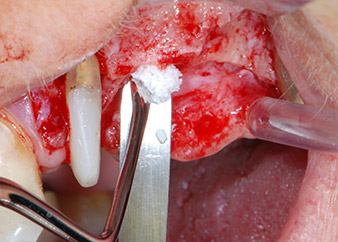

Vor der Insertion der Implantate und nach Überprüfung der intakten Schneiderschen Membran (Abb.9) wurde der interne Sinusboden an beiden Implantatpositionen mittels eines xenogenen Knochenersatzmaterials (Abb. 10) augmentiert.